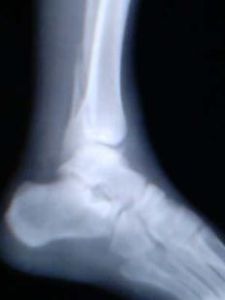

局部腫脹、壓痛和功能障礙。診斷時,首先應根據外傷史和臨床症狀以及 X 線片顯示的骨折類型,分析造成損傷的機制。

I 度:單純內踝骨折,骨折緣由脛骨下關節面斜上內上,接近垂直方向。

II 度:暴力較大,內踝發生撞擊骨折的同時,外踝發生撕脫骨折,稱雙踝骨折。

III 度:暴力較大,在內外踝骨折同時距骨向後撞擊脛骨後緣,發生後踝骨折(三踝骨折)。

I 度:單純內踝撕脫骨折,骨折線呈橫行或短斜行,骨折面呈冠狀,多不移位。

II 度:暴力繼續作用,距骨體向外踝撞擊,發生外踝斜行骨折,即雙踝骨折。如果內踝骨折的同時脛腓下韌帶斷裂,可以發生脛腓骨下端分離,此時距骨向外移位,可在腓骨下端相當於聯合韌帶上方,形成扭轉外力,造成腓骨下 1/3 或中 1/3 骨折,稱為 Dupuytren 骨折。

踝骨骨折III 度:暴力過大,距骨撞擊脛骨下關節面後緣,發生後踝骨折,即三踝骨折。